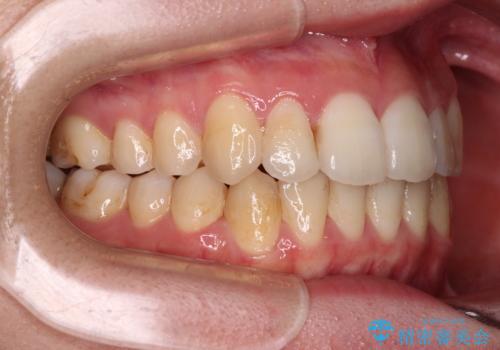

【モニター】前歯の前突感とクロスバイトをインビザラインで改善

- 前歯の突出感とクロスバイトが気になり、インビザラインによる矯正治療を希望して来院された患者様です。

上顎側切歯(上の真ん中から2番目の歯)が舌側転位している場合、インビザラインでは仕上げきれないことが多く、更には無理して動かそうとすると歯髄壊死を起こすリスクが高いと言われています。

インビザラインで歯列を移動する前に、上顎前歯をワイヤー矯正で整え、その後上下歯列をインビザラインにて矯正治療を行うこととしました。

舌側転位している側切歯特有の、切縁の位置が不揃いであったり、根元が内側に引っ込んだ状態であったりという、インビザライン独特の仕上がりになることなく、きれいに整った歯列とすることができました。